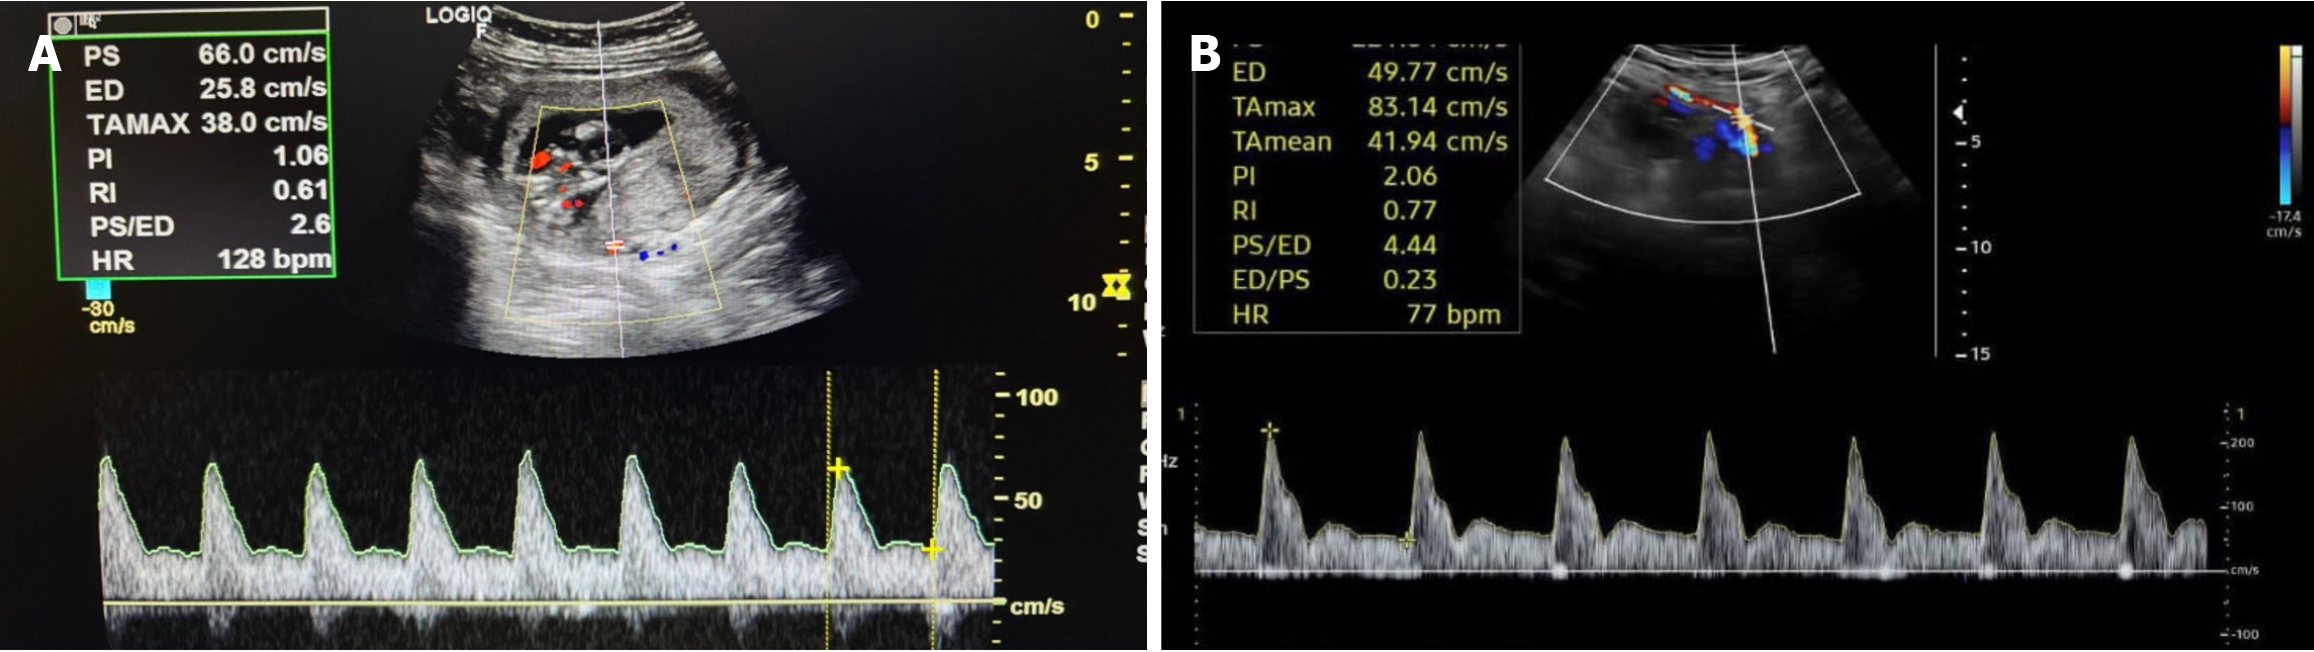

Figure 2 Normal and abnormal uterine artery Doppler at 13 weeks of gestation.

A: Uterine artery Doppler waveform in a 13-week pregnant woman with normal pregnancy outcome; B: High pulsatility index in uterine artery with presence of diastolic notching in a 13-week pregnant woman who subsequently developed pre-eclampsia. PS: Peak systolic velocity; ED: End diastolic velocity; TAmax: Time-averaged maximum velocity; PI: Pulsatility index; RI: Resistive index; HR: Heart rate; TAmean: Time-averaged mean velocity.